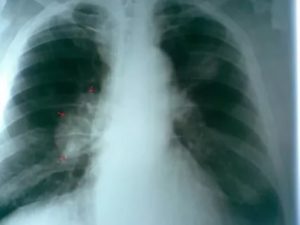

В первую очередь отмечается выраженное снижение структуры корней органа, их границы нечеткие, как у здорового человека, стенки бронхов утолщенные. При тяжелой степени заболевания у пациентов развивается обструкция.

В этом случае бронхит на рентгене будет иметь дополнительные признаки:

- Уплощенная грудная клетка.

- Низкое расположение диафрагмы.

- Ограничение подвижности диафрагмы.

- Легочный фон имеет повышенную прозрачность.

- Сердечная мышца располагается вертикально.

Рентген легких при бронхите с обструкцией выглядит следующим образом:

Воспаление бронхов с обструктивным синдромом характеризуется:

- повышенной воздушностью легких,

- низким стоянием диафрагмы,

- уплощением диафрагмы и ограничением её подвижности,

- вертикальным расположением сердца.